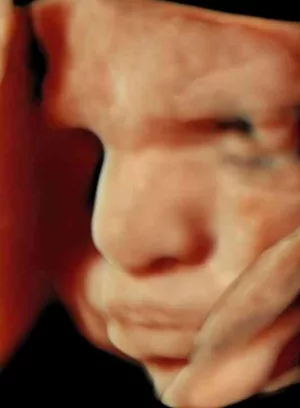

Ein erstes Lächeln? Hochauflösende Ultraschall-Aufnahme eines Ungeborenen in der 31. Schwangerschaftswoche.

DEGUM/ E. Merz

Lächeln im Mutterleib

Gegen Ende des zweiten Schwangerschaftsdrittels haben Eltern gute Chancen, ihr Kind auf dem Ultraschallbild sogar lächeln zu sehen. Mitunter verzieht es auch die Mundwinkel, runzelt die Stirn und schaut missmutig oder traurig aus. „Die Bilder erscheinen sehr lebensecht und es ist kein Wunder, dass sie uns innerlich berühren“, sagt Merz. Viele Eltern fragen sich dann, ob sie sich Sorgen machen müssen: Ist ihr ungeborenes Kind womöglich unglücklich?

Doch der Experte von der Deutschen Gesellschaft für Ultraschall in der Medizin (DEGUM) beruhigt: Bei den Ungeborenen spiegelt der Gesichtsausdruck nach heutigem Wissen noch keine Gefühle wider. Stattdessen ist das Lächeln oder Stirnrunzeln das Ergebnis unwillkürlicher, reflexhafter Bewegungen. „Die Bewegungen sind eher eine Art Training“, erklärt Merz. Ein Lächeln bedeutet daher nicht, dass ein Baby glücklich ist und eine traurige Mine verrate nichts über schlechte Gefühle des Ungeborenen.